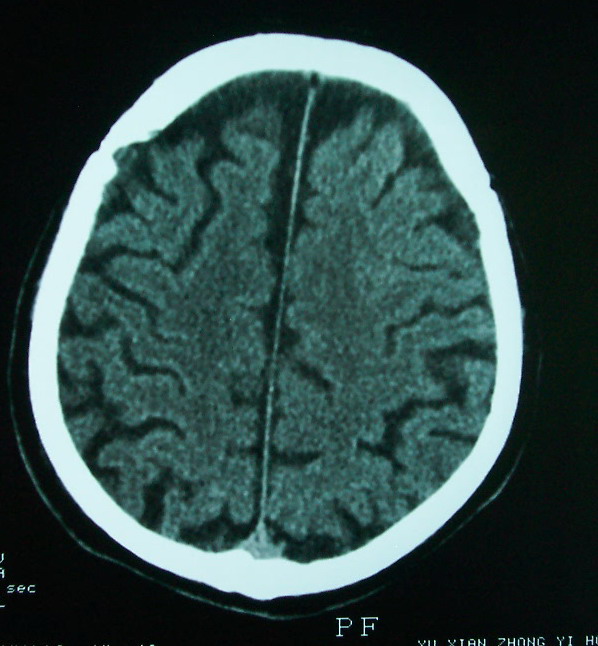

以下是引用余辉在2009-4-15 20:49:00的发言:[br]右侧病灶发生于冠状缝区,但额骨左侧鳞也有病灶,病灶区脑沟裂增宽(有脑萎缩征像,把这个征像放在颅骨病变一起考虑可能有点牵强),是否可能是板障血管畸形所致谢?抑或是嗜酸性肉芽肿或蛛网膜粒压迹那类东西?

以下是引用whzht在2009-4-15 20:57:00的发言:[br]1、额骨改变,考虑蛛网膜粒压迹;[br]2、脑萎缩。